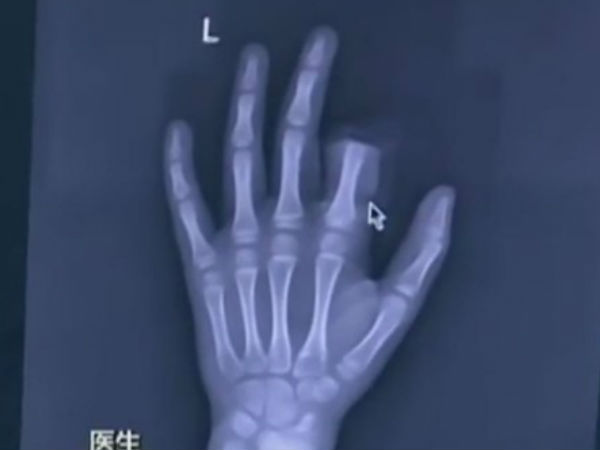

తల్లిదండ్రులు ఫోన్ వాడొద్దన్నందుకు మనస్థాపానికి గురైన ఓ 13ఏళ్ల బాలుడు తన చూపుడు వేలును కత్తిరించుకున్నట్లు గీక్డాట్కామ్ ఓ కథనంలో పేర్కొంది. ఉదయం లేచిన దగ్గర నుంచి ఈ బాలుడు ఫోన్తోనే గడుపుతుండటంతో తల్లి మందలించిందట. ఆ తరువాత కొద్ది సేపటికే తండ్రి కూడా మందలించటంతో మనస్థాపానికి గురైన బాలుగు వంట గదిలోకి వెళ్లి చాకుతో తన చూపుడు వేలును నరక్కున్నాడు. బాలుడుని వెంటనే సమీపంలోని ఆసుపత్రికి తరలించటంతో తెగిన వేలును తిరిగి అంటించేందుకు వైద్యులకు 3 గంటలు సమయం పట్టిందట.